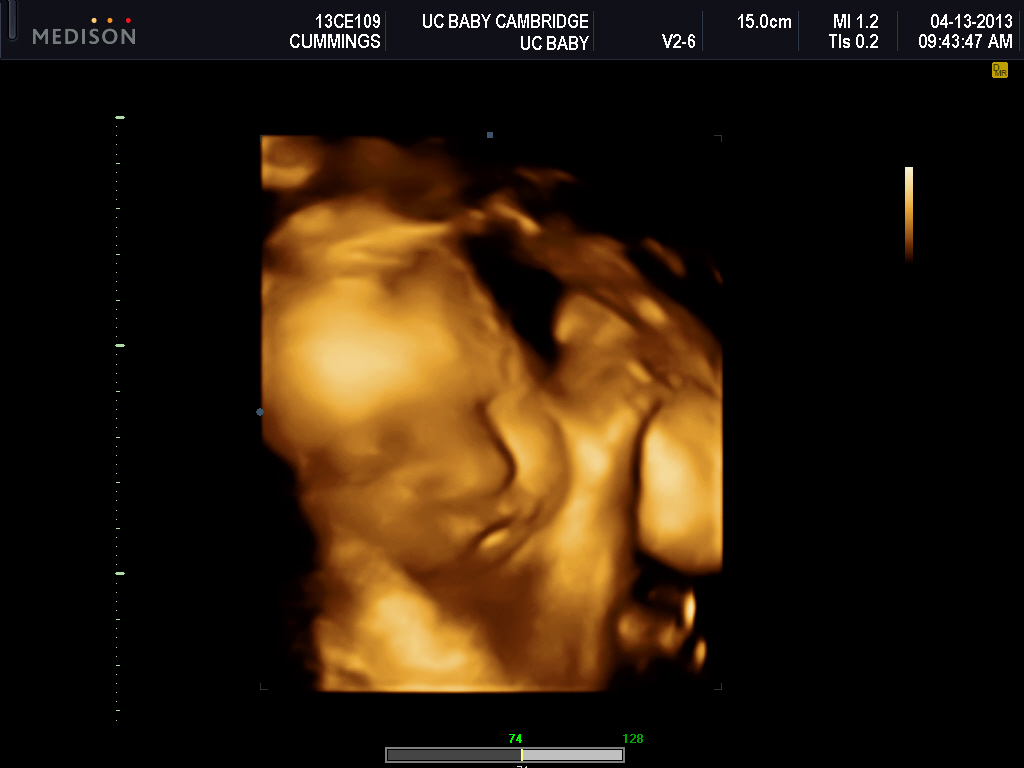

Best Moment of the Week: 3D ultrasound....so awesome to see our baby girl!

We had our 3D ultrasound yesterday morning, it was really great to see that baby girl is a healthy, busy baby despite all the recent craziness. She had her hands in front of her face most of the time which the tech said is pretty normal. She was moving like crazy, and yawning, and trying to put her whole hand in her mouth...haha! It was pretty neat that our families were able to watch it online. Of course, both of our families think she looks like us. Andrew and I just think she looks like a baby....hahaha!

Here's some of the pics we got:

Mouth open:

No hands in front of her face!:

My mom and sister think she's got my nose:

Thumb-sucking:

Andrew's sisters think she's got Andrew's cheeks:

Yawn: